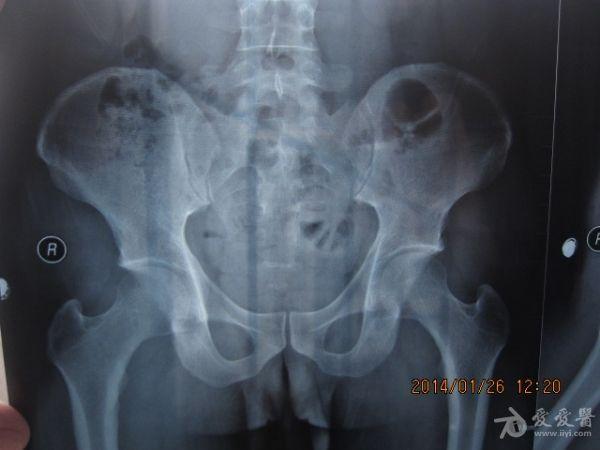

请老师看看这个腰椎和盆骨的平片有无问题

摔了一跤右臀着地,同时闪到腰,查出有椎间盘突出,目前是右臀麻木,整个右腿酸胀沉重。肌力正常走路正常,坐不到5分钟右腿就酸胀难忍。明显觉得左右**感觉不一样,右边软得多,

自觉下腰和盆骨感觉别捏,有歪斜感,扭腰时觉得舒服。腰4右侧一下有异物感。今天照了个腰椎正侧位和盆骨的正位平片,医生说没什么问题,拿来请各位老师看看腰椎和盆骨有没有错位,旋转,不等高等情况,再次感谢。

照该片看应该是骨盆旋移

这种症状拍平片没有什么意义,选择MRI或者CT吧

看片子没发现什么大的问题,没有骨折,没有增生。腰椎间盘突出做核磁共振最清楚。